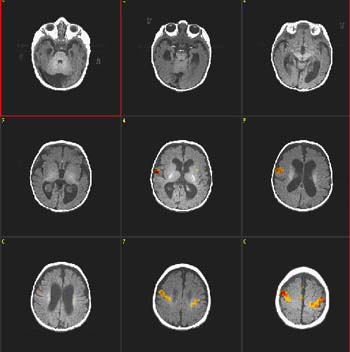

| Caso 1 |

| Paciente |

Niña de 2 meses de edad con hidrocefalia |

| Paradigma |

ACTIVADO: Presentación de la voz de la madre, pregrabada, en la que usa palabras familiares

DESACTIVADO: Nada. Paciente sedado con hidrato de cloral |

| Estadísticas |

| Método estadístico |

Valor P |

Puntuación Z |

| Prueba T |

0,0007 |

3,4 |

| Activación |

Se observa activación bilateral de las circunvoluciones precentrales y la circunvolución temporal superior derecha. La activación de la corteza motora ocurre en el nivel de la representación oral-facial. Se supone que esto está relacionado con el acostumbramiento-desacostumbramiento a la succión de amplitud alta en respuesta a estímulos lingüísticos. Esta respuesta es de gran importancia en la preservación de nuestra especie. |